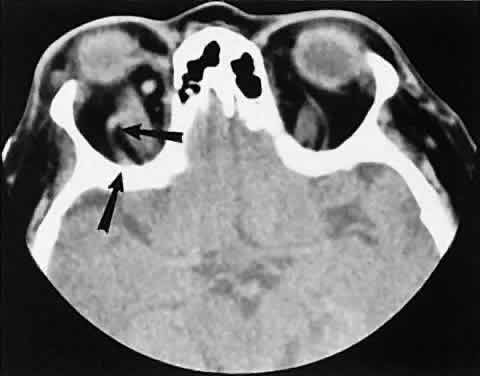

The orbital manifestations of a vascular process are dependent on whether the lesion is on the venous or the arterial circulation. Patients with venous lesions (varix) characteristically report a history of intermittent proptosis with either a Valsalva's-type maneuver or having the head in a dependent position. Suspicion of a venous varix should alert the radiologist to perform the scan before and after a Valsalva's maneuver.9,10 Color flow doppler imaging showing reversal of flow during a Valsalva maneuver also is a helpful finding. Phleboliths may or may not be present. Another clue to the diagnosis of a varix is the location, many times in the posterior, inferior lateral orbit, seemingly coming out of the inferior orbital fissure near the apex. Lesions that appear to change size or shape from the axial view to the coronal view also have turned out to represent a varix based on our experience (Fig. 2).

Fig. 2. Orbital varix. A. Axial view shows a small soft tissue mass within the inferolateral left orbital apex. B. Coronal view with patient repositioned prone with neck extension. Increased venous pressure distends the varix, accounting for increased size.